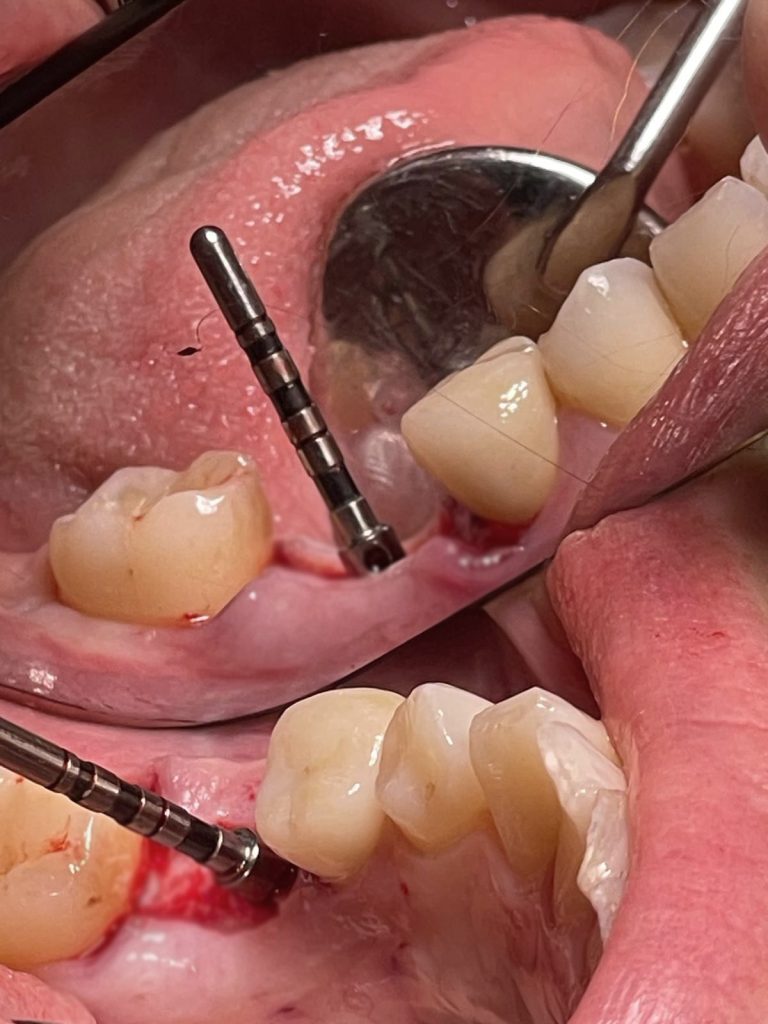

Nel caso che vi presento oggi mi preme sottolineare quanto il risultato di un intervento di implantologia derivi principalmente dal corretto posizionamento dell’impianto stesso.

In questo caso specifico, con l’impianto PRAMA di Sweden&Martina è possibile gestire il posizionamento in senso apico-coronale per poter tenere la connessione impianto/abutment sovracrestale; in questo modo è possibile tenere l’eventuale infiltrato batterico lontano dal tessuto osseo.